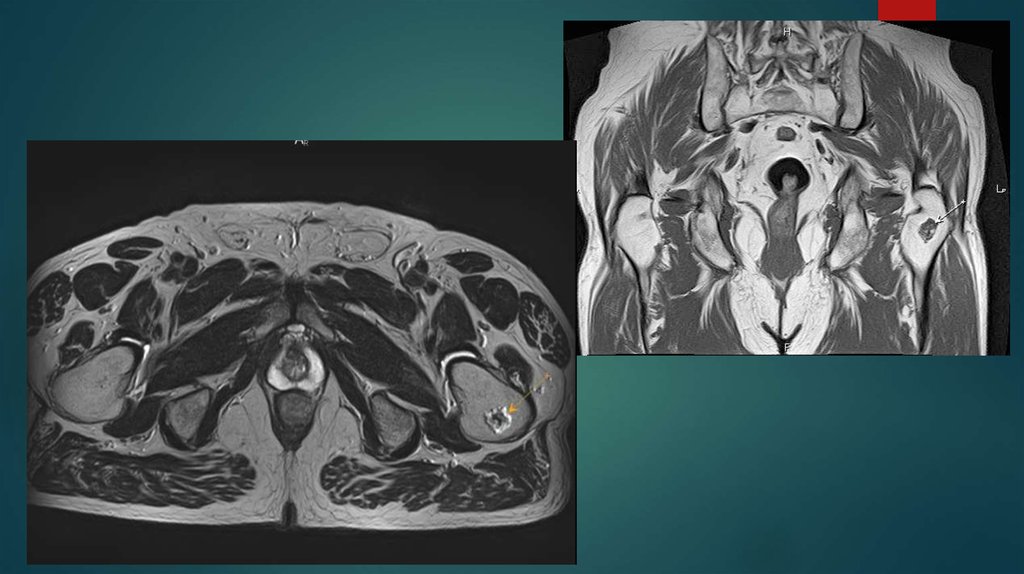

Назовите метод исследования и опишите результат.